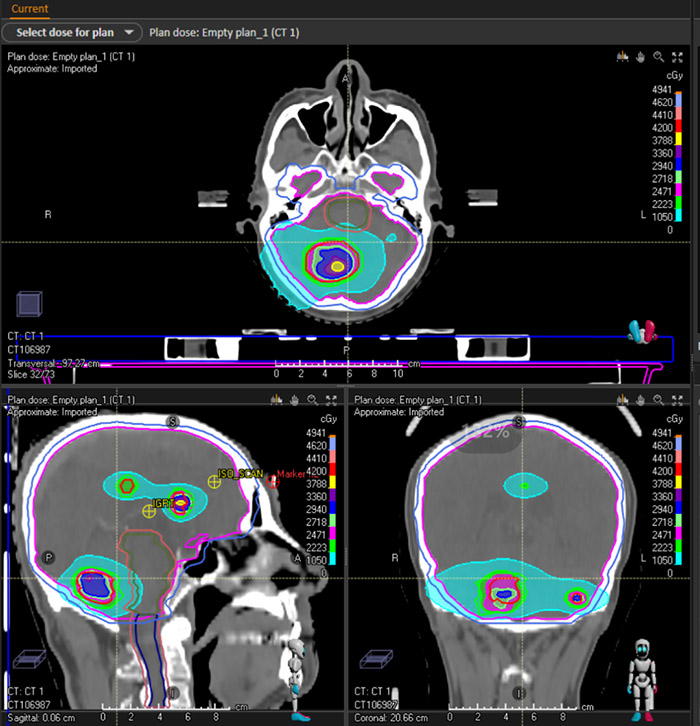

以下是一例肺癌多发脑转移病例的伽玛刀+直线加速器双头计划。通过DVH图以及剂量分布可以发现,比传统的直线加速器治疗,患者靶区的剂量得以提高,危机器官受量相对减少,达到了更佳的临床治疗效果。

剂量分布图

伽玛刀剂量分布图

直线加速器剂量分布图